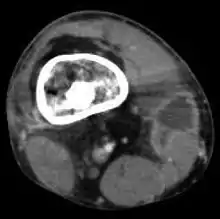

Mycobacterium doricum osteomyelitis and soft tissue infection. Computed tomography scan of the right lower extremity of a 21-year-old, showing abscess formation adjacent to nonunion of a right femur fracture.